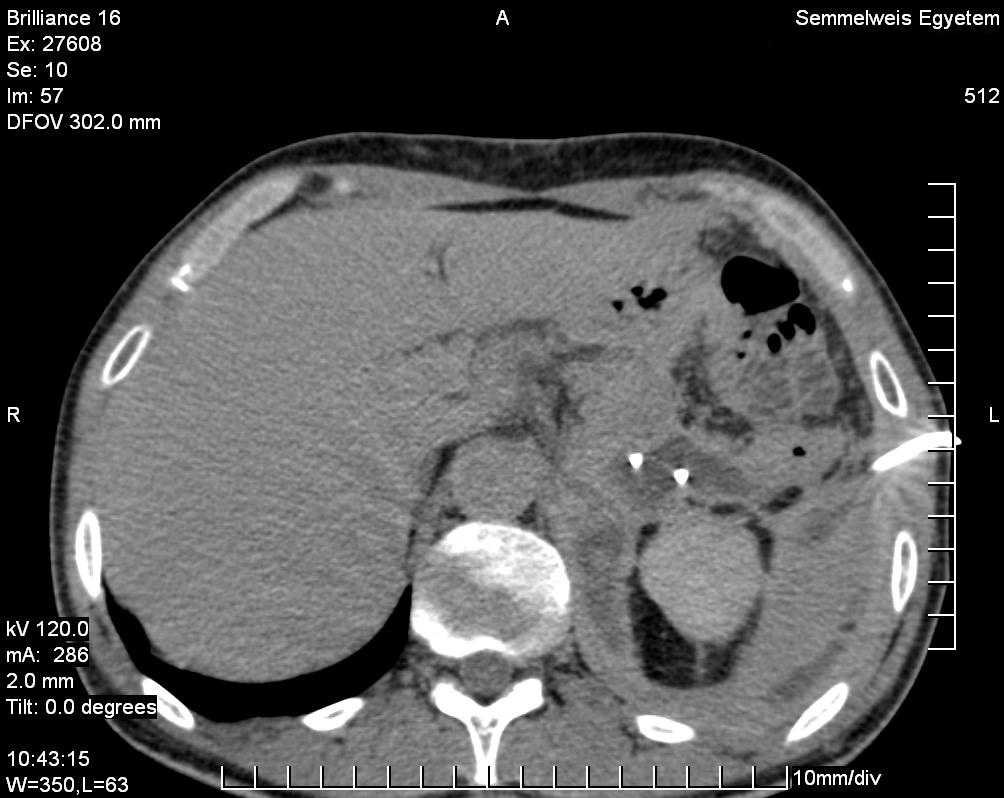

14.1.1.3. CT

Nowadays, CT is a basically important method amongst the modern diagnostic imaging services. (Figure 4) By the application of the multidetector CTs a chance is given to perform multiphase (without contrast, arterial, portal and late phase) CT scans, which provide important additional information because of the different hemodynamics of certain intrahepatic nodules. Multiplanar (sagittal, coronal, oblique) and 3D reconstructions can be adopted from the axial plane CT slices. Due to CT angiographic techniques, excellent spatial resolutional 3D reconstructional images can be performed both on the arterial (hepatic artery) and the venous sides (portal vein, hepatic veins, collateral veins in case of portal hypertension, CT control of transjugular portosystemic shunts)..

Figure 4. Liver, contrast enhanced CT, venous phase